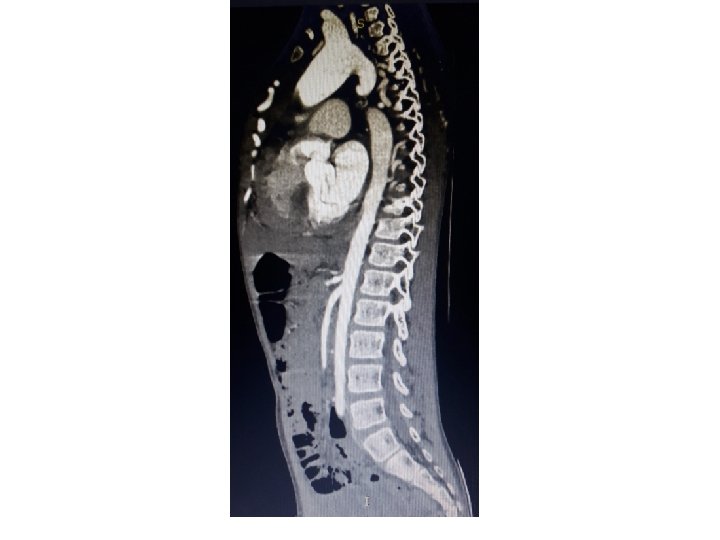

Interrupted aortic arch

Celoria and patten classification

Type A (30 -44%) Aorticopulmonary septal defect and intact ventricular septum, TGA with IVS Type B (51 -70%) • More common • a/w conotruncal anomaly with normally aligned great arteries • Large malalignment-type VSD • Posterior displacement of the infundibular septum and subaortic obstruction Type C Very rare